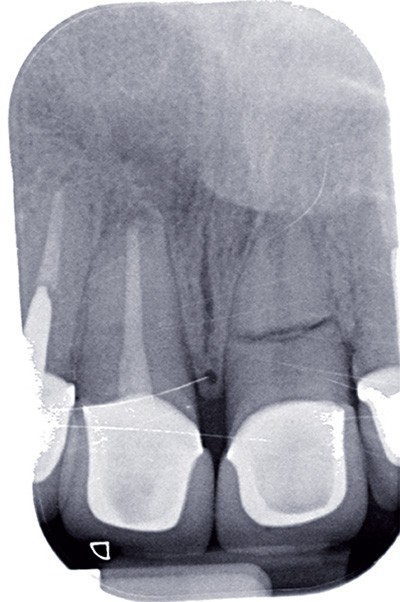

Avant de répondre aux différentes interrogations cliniques, il faut analyser la situation par des évaluations cliniques (état coronaire, situation endodontique, environnement parodontal) (fig. 1) puis, parfois, il est nécessaire de poursuivre cette étude préthérapeutique à l’aide d’outil de simulation comme l’articulateur (fig. 2), de techniques radiologiques en 3D. La conjugaison du recueil des informations et de l’analyse de la situation va nous permettre de proposer une solution en rapport avec la problématique médicale globale.